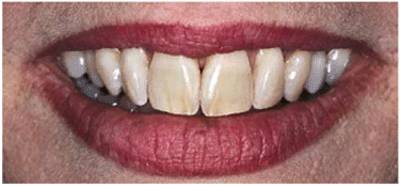

either on an individual tooth or on all teeth (Figures 16-1A, and 16-1B). There are many causes and

Figure 16-1A: An otherwise attractive smile is marred by discolored teeth.

Figure 16-1B: After tooth lightening, the smile is much more pleasing.